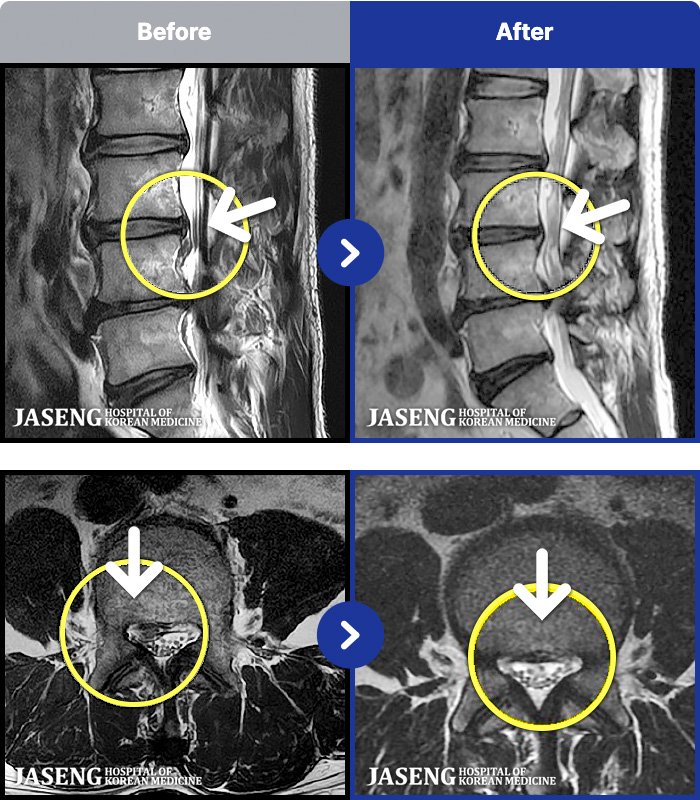

54 MRI ũ ʸ Ȯϼ.